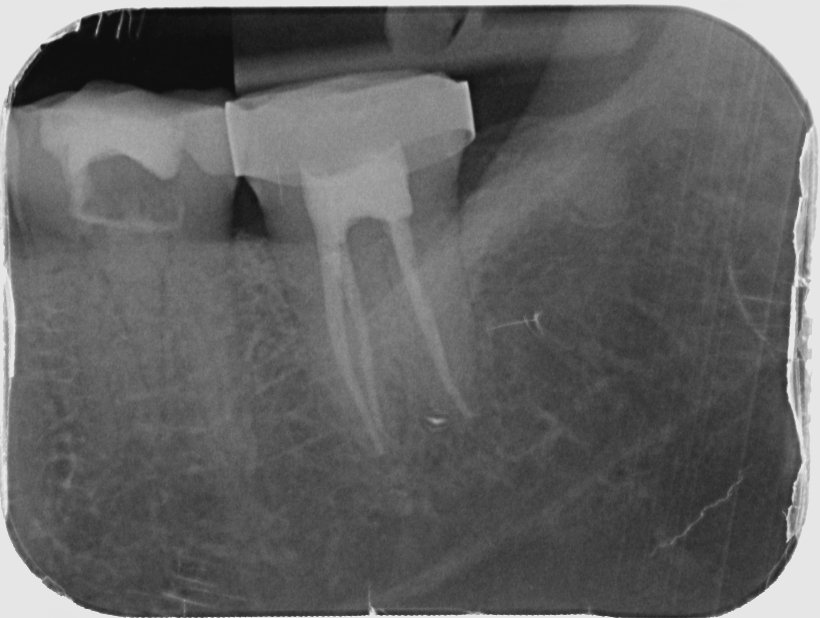

Endodontics